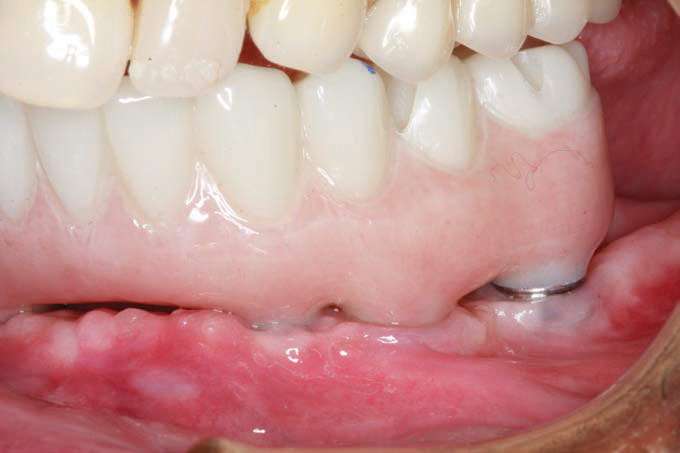

The final monolithic zirconia restoration was fabricated based on the same digital design as the approved PMMA provisional, allowing the patient and his wife easy access for all cleaning implements. The patient had little food impaction and was comfortable with his border movements and ability to really cut and chew his food.

The completed BruxZir Full-Arch Implant Prosthesis is the culmination of great communication with the dental lab team. The final prosthetic result ensured that the patient would not only enjoy his new bridge but would also be able to clean and maintain it with one hand (Figure 20). The relaxed smile view and postoperative Panorex (Figures 21 and 22) shows appropriate lip and tooth display and was a vast improvement over his removable lower denture. The full-face, postoperative photo (Figure 23) of the pleased patient demonstrates that the dictates of aesthetic rehabilitation were met.